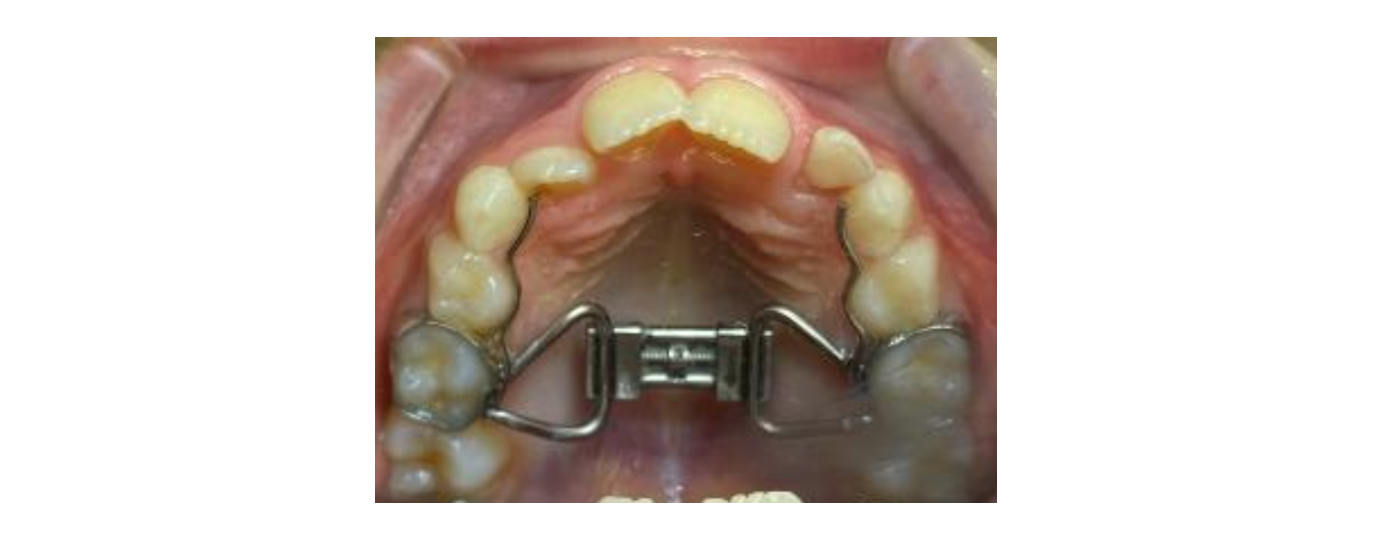

Rapid Palatal Expansion Appliance

Rapid Palatal Expansion Appliance from an orthodontist alio loco

So,  we did 9 months of Schwartz appliance.  My biggest concern though, from the beginning of this story was that this appliance ONLY addresses the upper jaw. After 9 months we reached the maximum expansion, which was  4 or 5 mm before Keyan would develop a scissor bite.

Usually, at Keyan’s age, a tooth-borne expander is enough to expand the upper jaw. The downside however, is, that 50% of the effects will be dental (teeth moving sideways) and only 50% will be the desired skeletal effects. For that reason, a bone-anchored expander was chosen to get 100% skeletal effects and maximize the improvement in the nasal cavity.